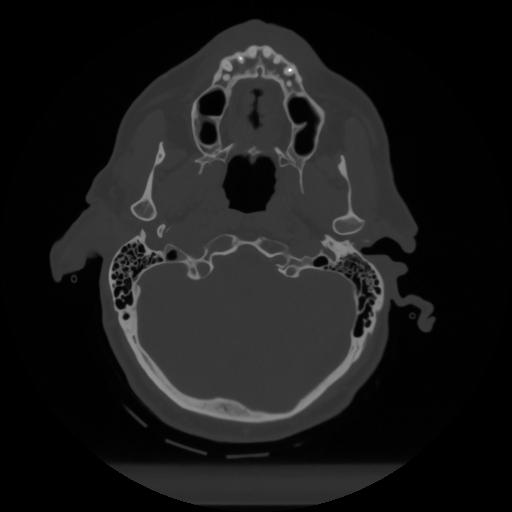

12 P.BLANDAS,,Vol,0.5,P.BLANDAS,,